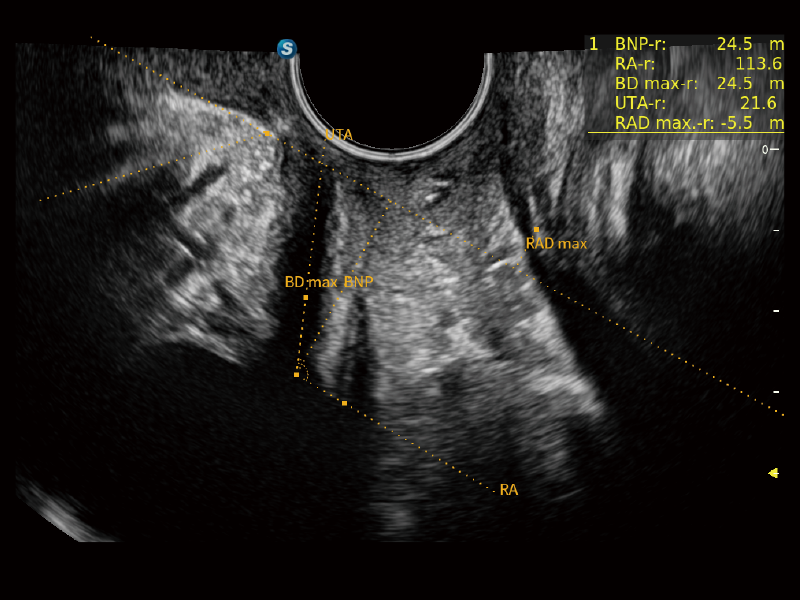

盆底自動(dòng)測(cè)量(2D)